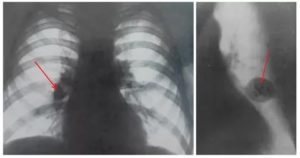

Опасным признаком является полициклически расширенный корень. Как правило, такая патология наблюдается с одной стороны. Полицикличность корню придают лимфатические узлы, которые располагаются по ходу крупных сосудов и бронхов.

Увеличение лимфатических узлов наблюдается чаще всего во время активного туберкулеза, но бывают и более редкие причины: саркоидоз и метастазы злокачественной опухоли.

Внимание. При этом, стоит помнить, что у молодых людей более вероятно наличие туберкулеза, а у пожилых – опухолевого процесса.

Иногда полициклически измененные корни являются первым проявлением метастазов онкологических заболеваний.

Внимание. Опухоли часто очень быстро начинают метастазировать в легкие и лимфатические узлы корня, потому такая находка становится первым этапом диагностики рака.